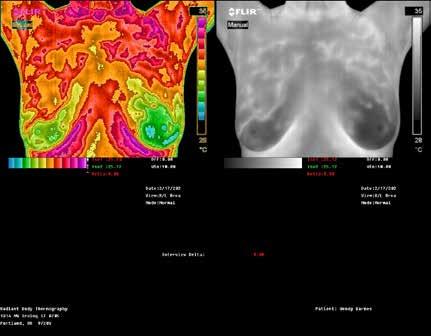

RADIANT BODY

THERMOGRAPHY

TOP: Thermographic pattern of physician confirmed estrogen dominance, which the client addresses. BOTTOM: Images show success in removing the estrogen dominance pattern & client also downgrades her abnormal right breast! Estrogen dominance has a heat signature visible with QUALITY Thermography.